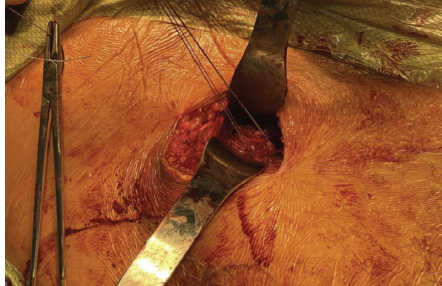

Dissection was carried down through the superficial Smith-Peterson interval between sartorius and tensor fascia lata. The avulsed rectus femoris tendon was then visualized – it was retracted approximately 4cm with an associated seroma, and there were residual attachments of the indirect head to the superior acetabulum. The tendon was tagged with sutures and mobilized with blunt dissection (Fig. 4).

Figure 4: Avulsed rectus femoris tendon tagged with mobilizations sutures.